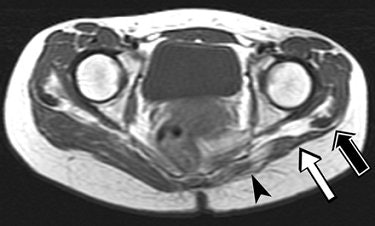

| A 23-year-old woman suffering from bilateral gluteal contracture that is more severe on left side. Patient related history of repeated injections in both buttocks since adolescence. Spin-echo T1-weighted axial image (TR/TE, 566/16) shows atrophic and medial retraction of left gluteus maximus muscle (arrowhead), thickening and retraction of fibrotic cord and distal tendon (white arrow), and displacement of iliotibial tract (black arrow). |

Among the 21 patients, 17 had a contracture of the bilateral gluteus maximus muscles while four had lesions on the right buttock only. All buttocks showed primary features of muscle atrophy and intramuscular fibrotic cord contiguous to the iliotibial track, which manifested as low signal intensity.

"Retraction of the thickened tendon and fibrotic cord accounted for the secondary MRI features," they wrote, such as medial retraction of the affected muscle and a depressed groove at the muscle tendon junction. "The muscle atrophy affected most commonly the upper third of the gluteus maximus, which is related to the injection technique."